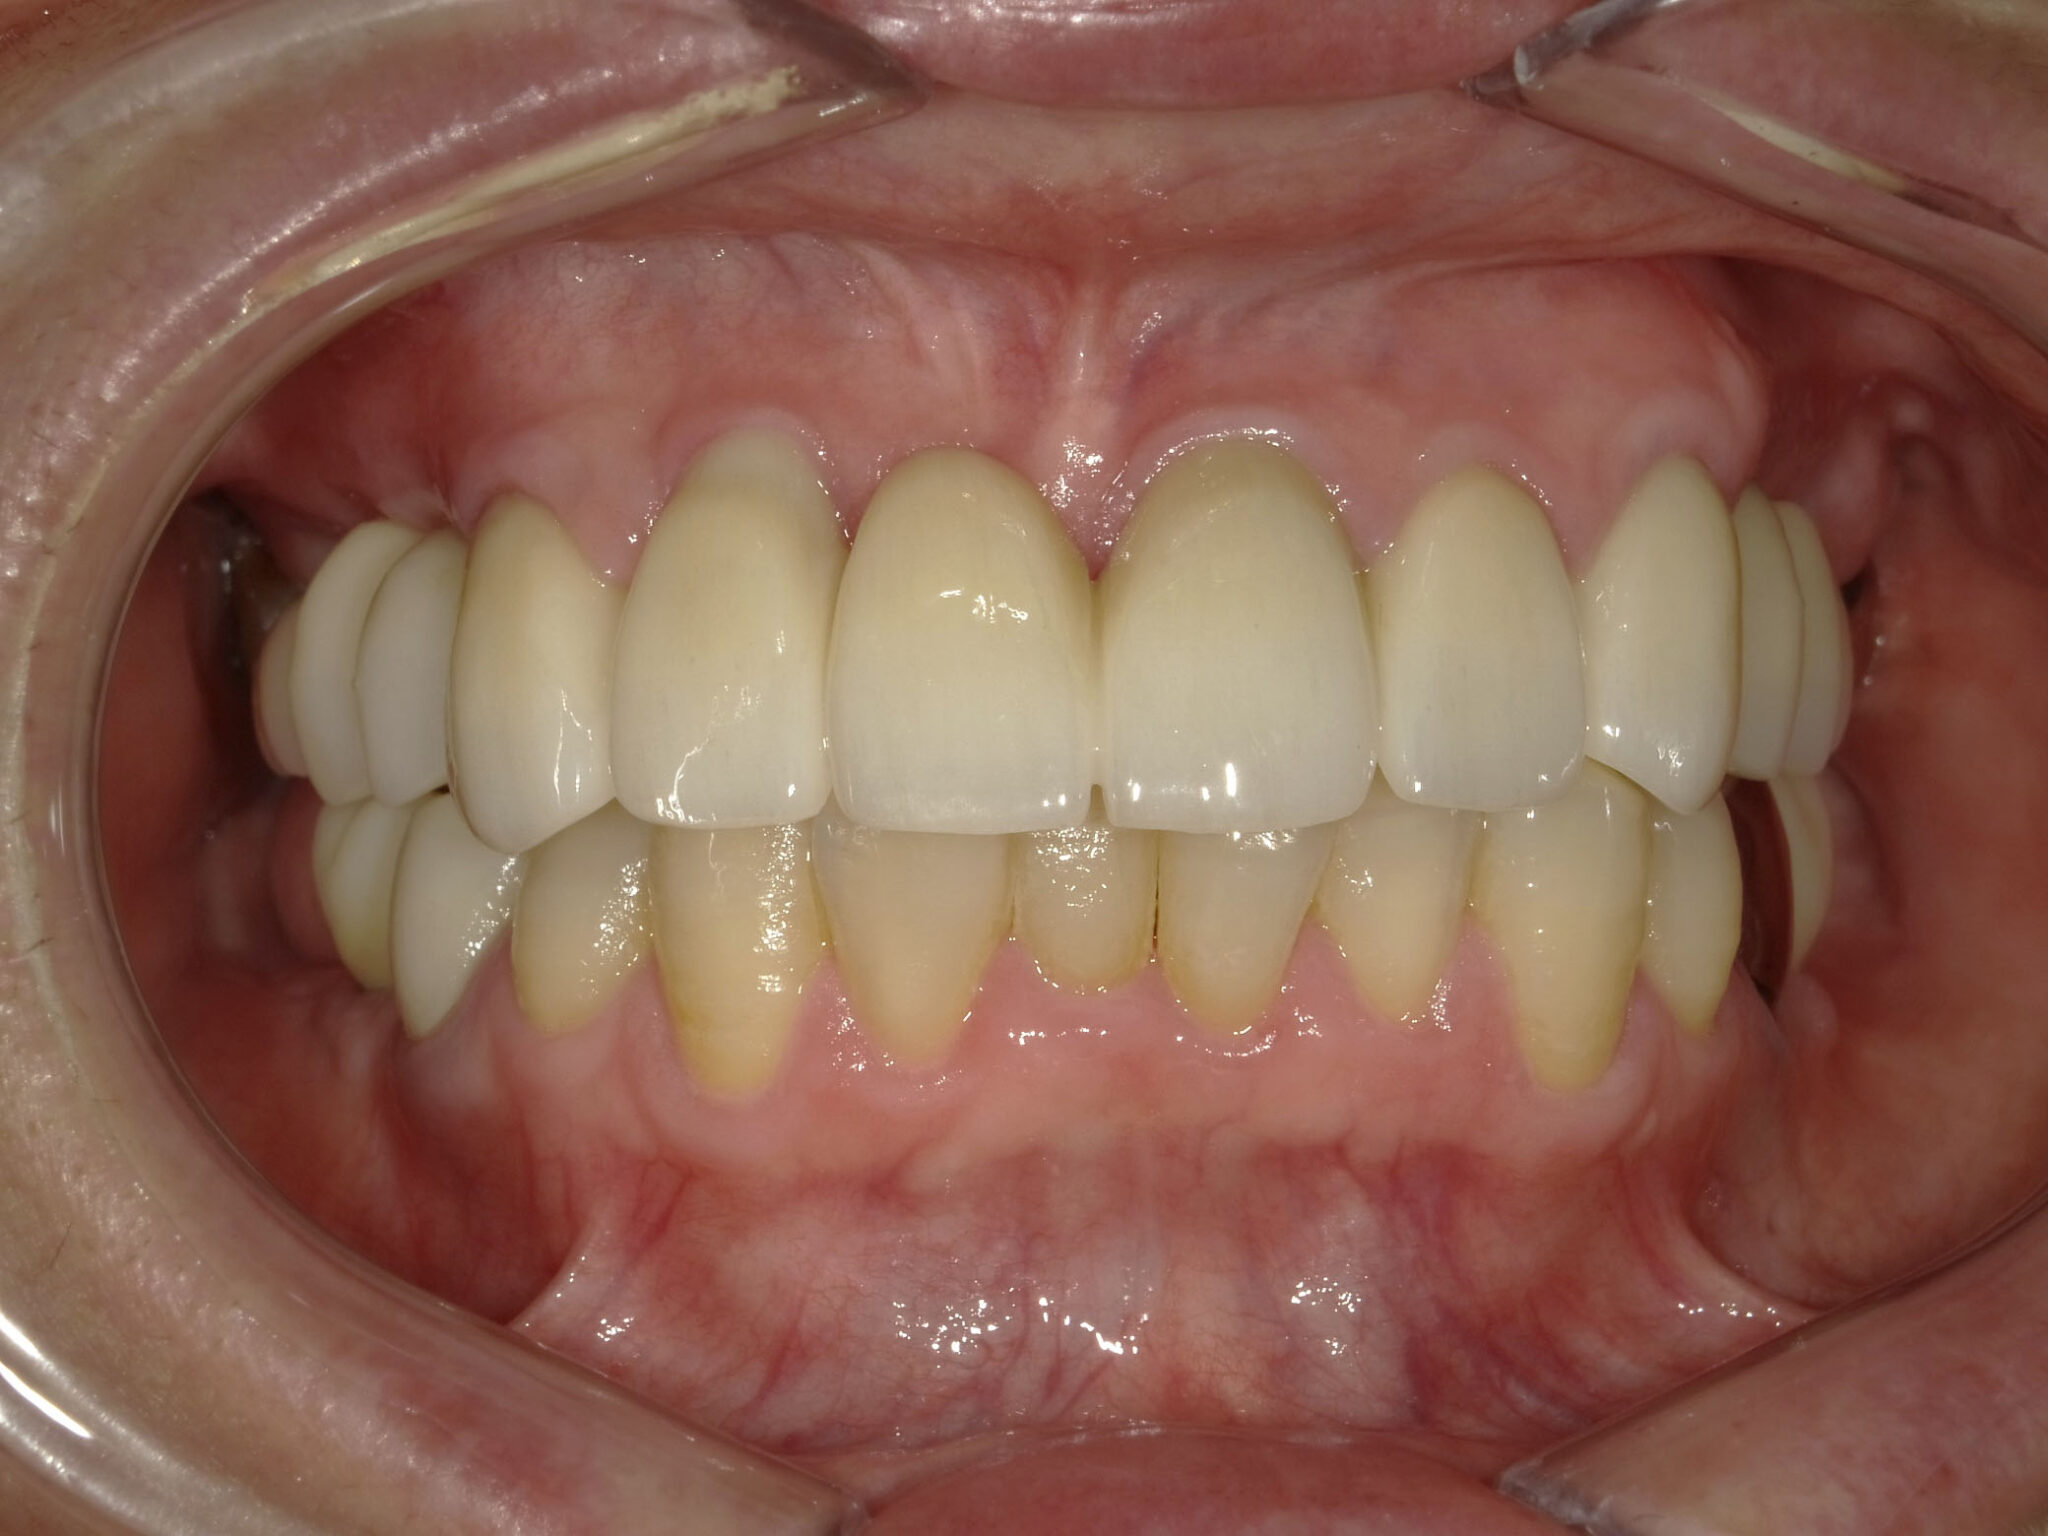

| 主訴 | 全体的に見た目を綺麗にしたい。奥歯でしっかり噛みたい。 |

| 治療内容 | インプラント埋入(右上4・6,左上4・6,右下6,左下6) ジルコニアBr(右上3―左上3) ジルコニア(右下5,左下5) |

インプラント 1年5ヶ月/13回 ジルコニアBr、ジルコニアクラウン 3ヶ月/10回 |